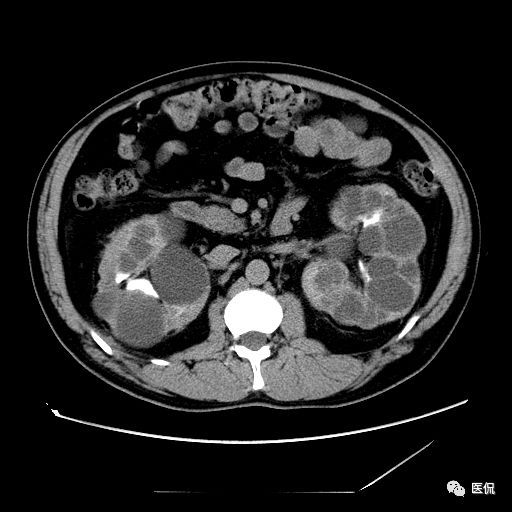

双肾实质可见多发囊性密度灶,其内密度不均匀,并可见钙化灶,增强扫描未见明显强化灶。肾周脂肪间隙清晰,与邻近组织分界清楚。

多囊肾的 CT 表现主要表现为双肾增大,轮廓光滑或有分叶,肾实质内多个大小不等的囊肿呈蜂窝状,多呈水样低密度,增强扫描囊肿本身无强化,而囊肿间正常肾组织增强,对比明显。当囊肿张力过高,使囊壁上毛细血管牵拉破裂出血时,表现为囊肿内稍高密度影,随访CT 值减低。囊壁钙化,表现为点线状高密度影像,随访CT值无变化。有文献报道约 30%病例可并发多囊肝或多囊胰。